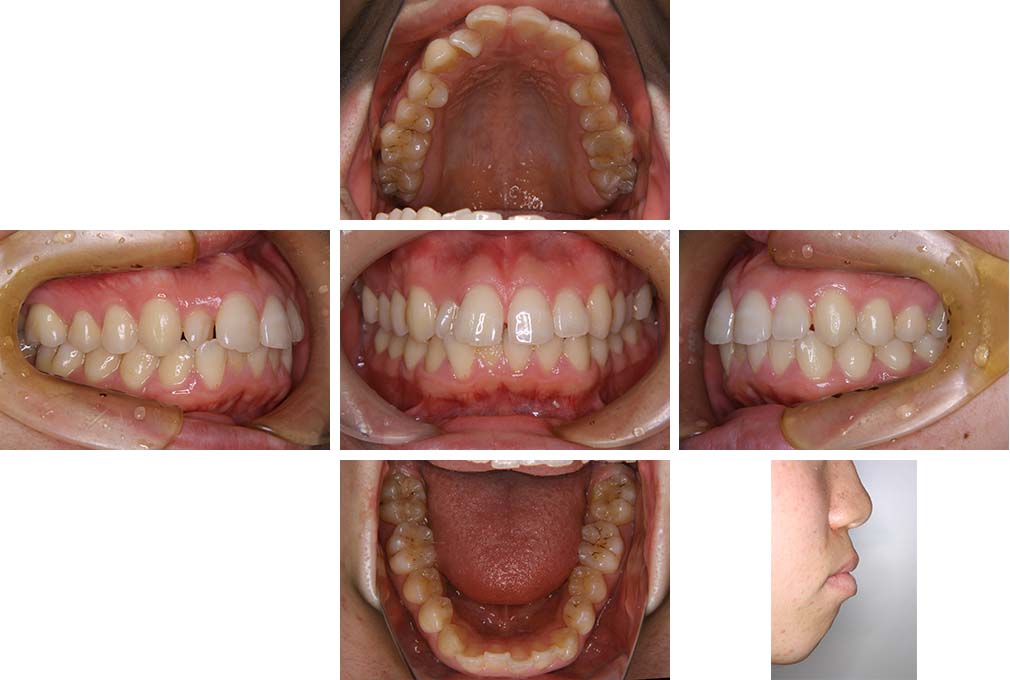

CASE:01

叢生を伴う骨格性上顎前突

初診時年齢 15歳10カ月

性別 男性

治療費の目安 約75万円程度(治療開始時)

上顎前歯の前突と叢生を主訴として来院された。大臼歯関係は左右側ともにⅡ級で上顎の方が前方に位置していた。叢生を伴う骨格性上顎前突と診断し、上下顎小臼歯抜歯を行っていただきマルチブラケット装置に顎外固定装置を併用して動的治療を行った。顎外固定装置や矯正用ゴムの使用など協力状態も良好で、動的治療期間2年0カ月、調整来院20回でマルチブラケット装置を撤去し保定へ移行した。動的治療終了後10年0カ月を経過したが保定移行時とほぼ同様の咬合状態で良好な状態を保っていた。

治療前

15歳10か月

治療後

動的治療期間2年0カ月

18歳5か月

10年経過

動的治療終了後10年0カ月

28歳5か月